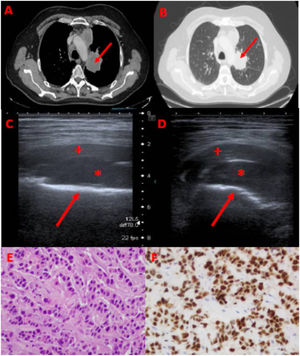

A y B) TC tórax: masa pulmonar central de 5,5 cm en lóbulo superior izquierdo (flecha). C y D) Ecografía musculoesquelética: masa de partes blandas de 10 x 3 cm (señalizada con asterisco), localizada entre la cortical anterior del fémur izquierdo (flecha) y el recto femoral izquierdo (cruz). E) Imagen de anatomía patológica (AP): tinción con hematoxilina-eosina. F) Imagen de AP: expresión positiva de TTF1 (origen pulmonar).

Presentamos el caso de un paciente de 56 años de edad, alérgico a tramadol, fumador de 35 paquetes/año, con antecedentes personales de dislipemia, artritis seronegativa, hernia discal L3-L4 y melanoma en rodilla derecha intervenido en 1984, que consultó por dolor en el muslo izquierdo que había ido aumentando progresivamente hasta imposibilitarle el sueño y la deambulación. En la exploración física presentaba aceptable estado general y la auscultación cardiopulmonar era normal. En el tercio medio de la cara anterior de la pierna izquierda se palpaba una masa de consistencia dura, dolorosa a la palpación, sin alteración dérmica. En la radiografía de tórax se visualizaba una masa central de al menos 5 cm en lóbulo superior izquierdo. La analítica sanguínea era anodina, salvo una proteína C reactiva (PCR) de 193 mg/L. El paciente ingresó a cargo de Neumología para completar estudio y control del dolor. Se realizó una tomografía computarizada (TC) de tórax y abdomen (fig. 1, A y B) donde se apreciaba una masa central hiliar izquierda de unos 5,5 cm de diámetro mayor que rodeaba el bronquio del lóbulo superior izquierdo, englobando y estenosando sus bronquios segmentarios, con obstrucción del bronquio del segmento 1-2 de dicho lóbulo. La masa englobaba y estenosaba también las ramas de la arteria pulmonar lobar superior izquierda. Además, se visualizaba una adenopatía supraclavicular izquierda de 16 mm (espacio 1L), adenopatías mediastínicas significativas en los espacios 7 (subcarinal), 2R y 4R (paratraqueales derechos) y adenopatías significativas hiliares derechas (espacios 10R y 11R). También se visualizaban lesiones líticas a nivel del cuerpo de la escápula derecha y cuerpo esternal compatible con metástasis óseas. Para la evaluación de la lesión del muslo izquierdo, se llevó al paciente a la Unidad de Broncoscopia y Técnicas Pleurales para realización de ecografía y, en función de resultados, valoración de biopsia a dicho nivel que permitiese a la vez el diagnóstico y la estadificación del tumor. En la ecografía de partes blandas con sonda lineal en modo B (fig. 1, C y D), se visualizó una masa heterogénea de aproximadamente 10 x 3 cm de diámetro localizada entre la cortical anterior del fémur izquierdo y el recto femoral izquierdo, en espacio anatómico de músculo vasto intermedio, que parecía estar desplazado anteriormente por esta masa. Con estos hallazgos, se procedió a realizar una biopsia con aguja gruesa (BAG) ecoguiada de la masa con aguja tipo Trucut de 18G, obteniéndose cuatro cilindros que se mandaron a anatomía patológica (fig. 1, E y F) con resultado de infiltración por carcinoma sugestivo de adenocarcinoma de origen broncopulmonar con ausencia de mutaciones del receptor del factor de crecimiento epidérmico (EGFR). Estudio inmunohistoquímico: ALK negativo, ROS-1 negativo, PDL-1 negativo (< 1%). Tras el diagnóstico de adenocarcinoma de pulmón T3N3M1c (estadio IV), se presentó en comité oncológico decidiéndose tratamiento con radioterapia con intención paliativa y quimioterapia con carboplatino-pemetrexed-pembrolizumab.